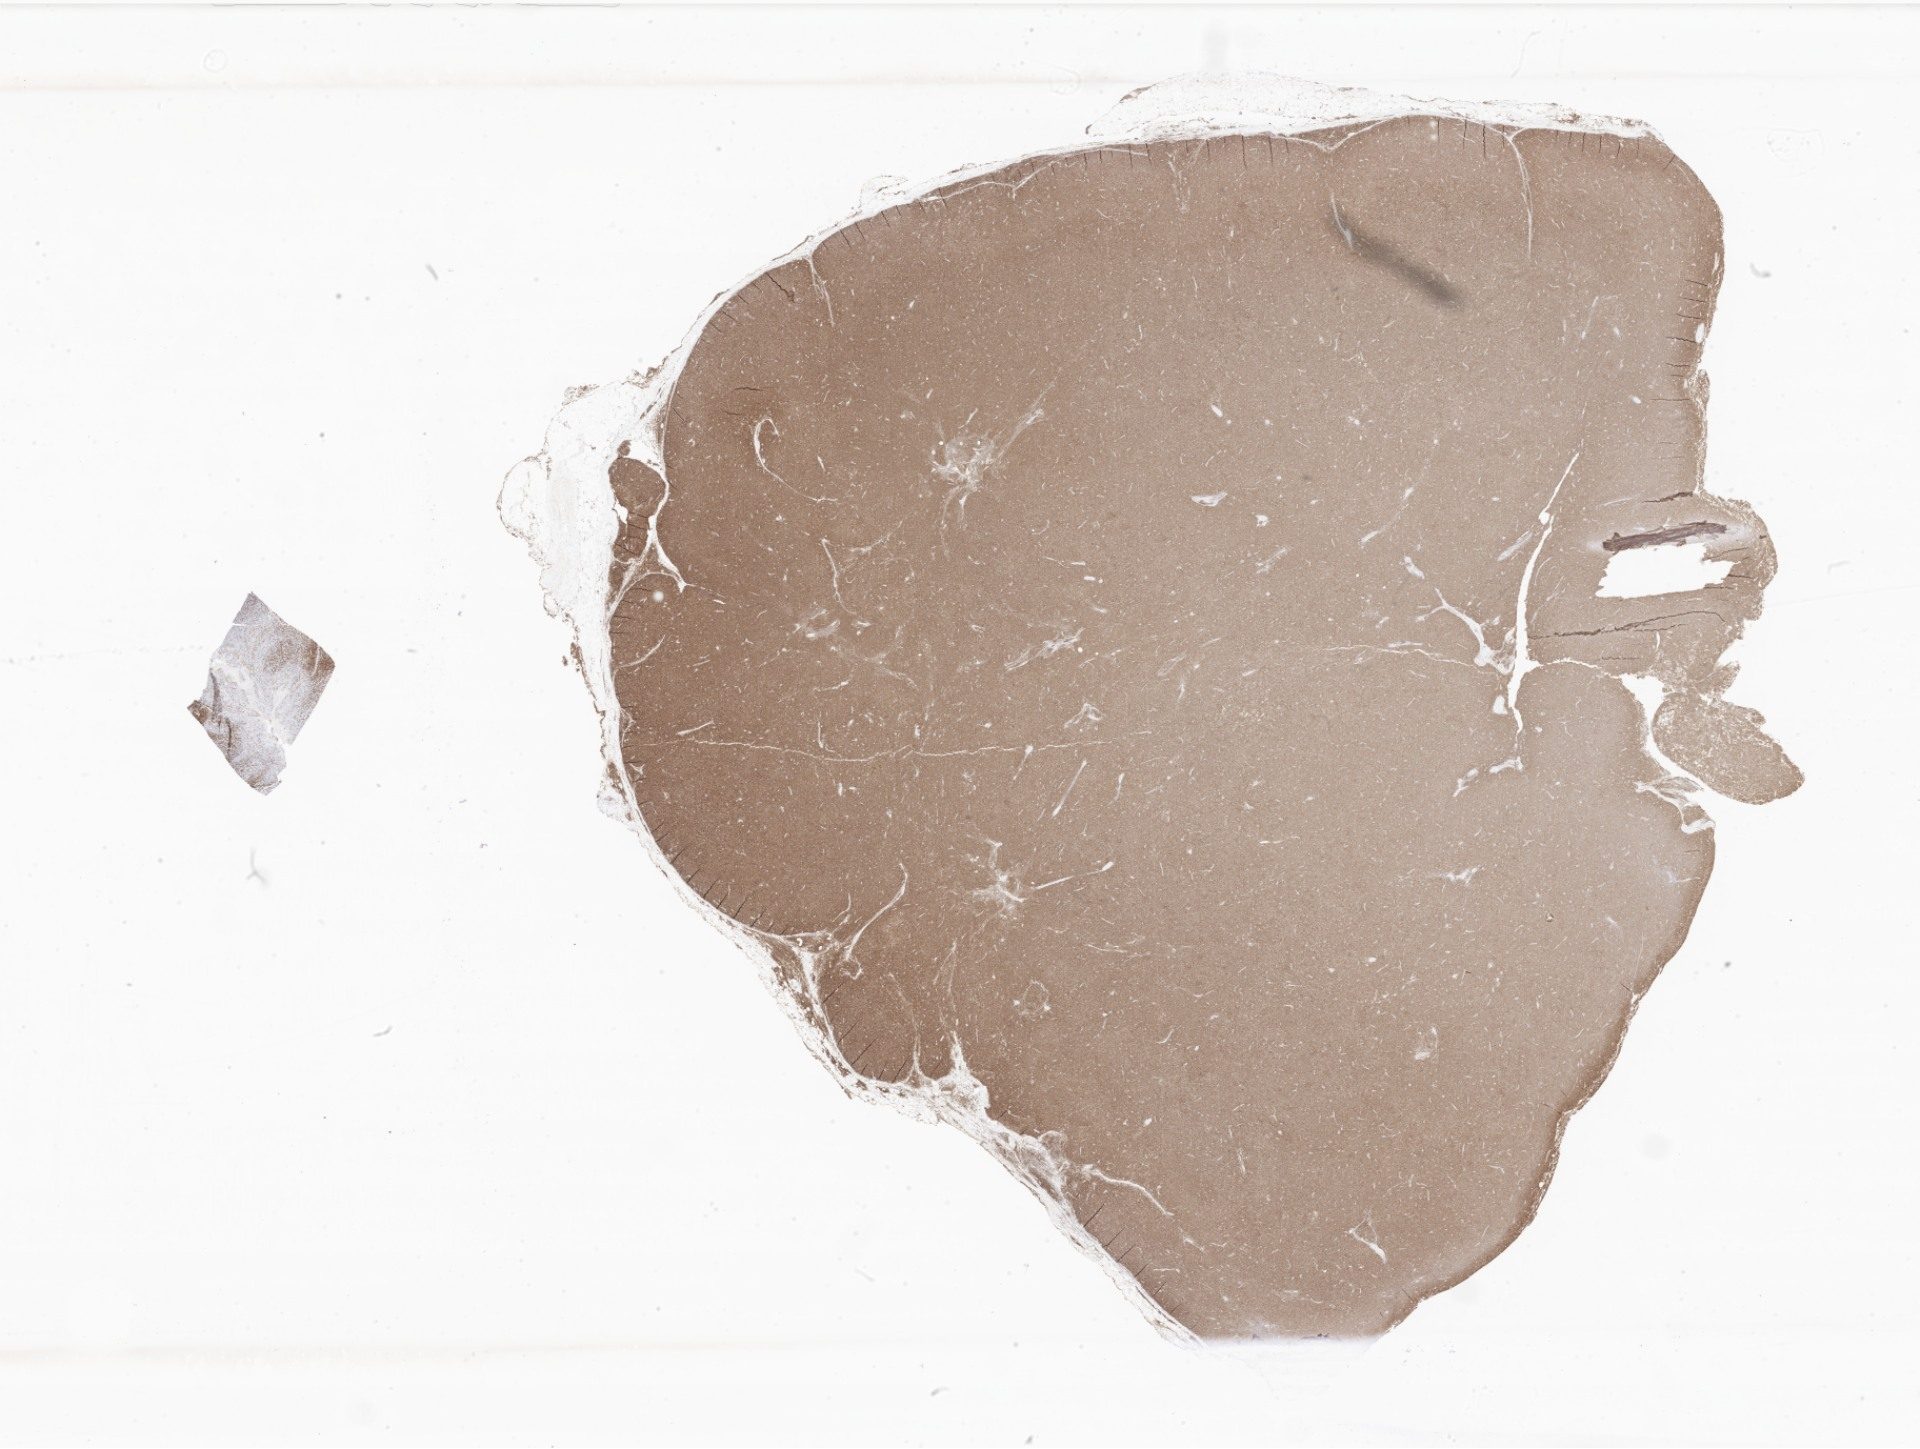

CD3.svs

167181

x

88098

@

40X